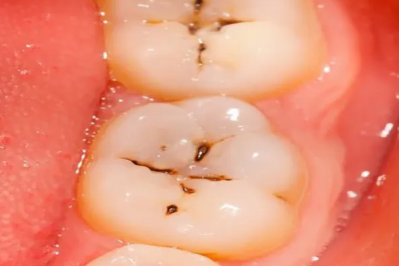

肠胃不好的注意了,阜康医院消化内科送你一份「养护宝典」!